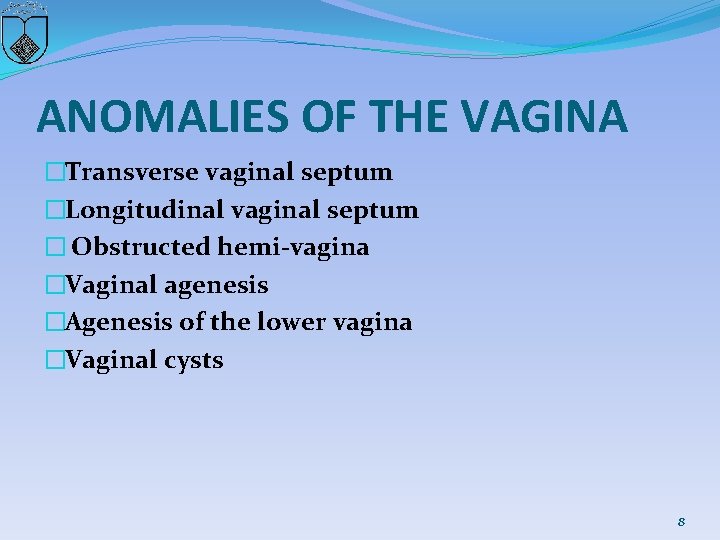

ANOMALIES OF THE VAGINA �Transverse vaginal septum �Longitudinal vaginal septum � Obstructed hemi-vagina �Vaginal agenesis �Agenesis of the lower vagina �Vaginal cysts 8